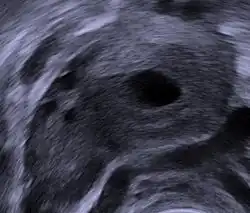

Human ovary with fully developed corpus luteum -